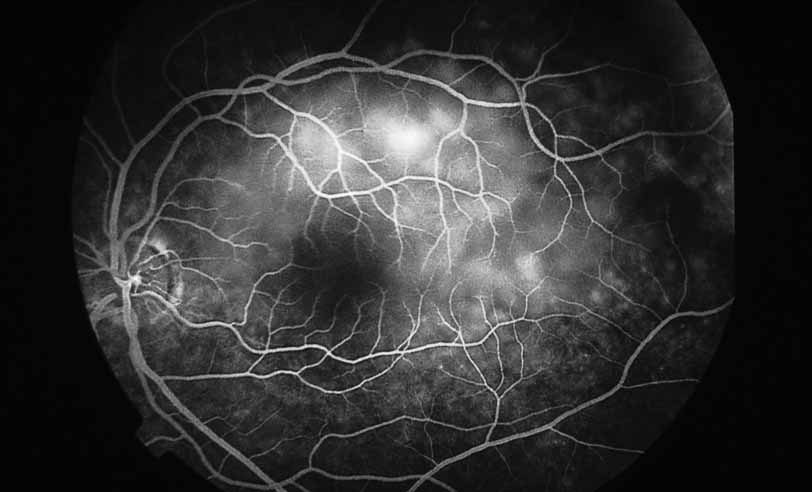

A variety of inflammations and infections, most notably presumed ocular histoplasmosis syndrome (see Figs. 37 and 38), serpiginous choroiditis, and multifocal choroiditis (see Figs. 39, 40, 41, and 42),1,89,90 are associated with the late complication of choroidal neovascularization. Probably the single most important application of fluorescein angiography in infectious and inflammatory diseases of the posterior segment is for the evaluation and potential treatment of this complication. In some instances, fluorescein angiography may be the single best method to determine whether visual loss seen late in the course of such disease as paramacular toxoplasmosis or serpiginous choroiditis is the result of secondary choroidal neovascularization or inflammatory disease recrudescence. In other diseases, such as presumed ocular histoplasmosis syndrome or multifocal choroiditis, choroidal neovascularization may occur early and be suspected on the basis of associated hemorrhage or lipid exudation. In some instances, even with the benefit of high-quality fluorescein angiography it may be difficult to distinguish between choroidal vasculitis and choroidal neovascularization superimposed on underlying choroiditis. We have recently identified a subgroup of young female patients, frequently darkly pigmented, who develop solitary zones of elevated choroiditis that have features of choroidal neovascularization. These appear to have a more indolent course than either idiopathic choroidal neovascularization or that associated with atypical multifocal choroiditis.

Fig. 40 Multifocal choroiditis. Fluorescein angiography confirms the presence of a subfoveal choroidal neovascular membrane.

Fig. 41 Multifocal choroiditis. Color photograph shows multiple small choroidal lesions scattered throughout the posterior pole.

Fig. 42 Multifocal choroiditis. ICG angiography shows multiple hypofluorescent spots in the distribution of the choroidal lesions seen on color photography.